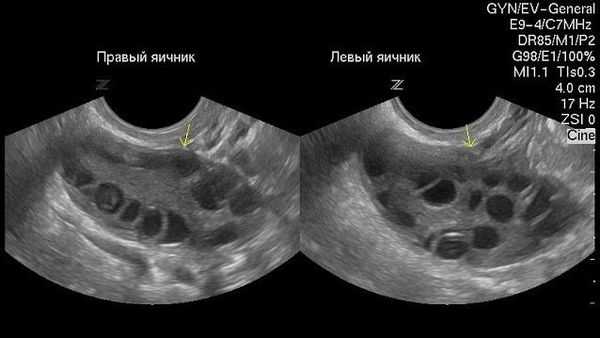

Как выглядят при ультразвуковом обследовании нормальные яичники:

Как выглядят яичники при наличии кист: